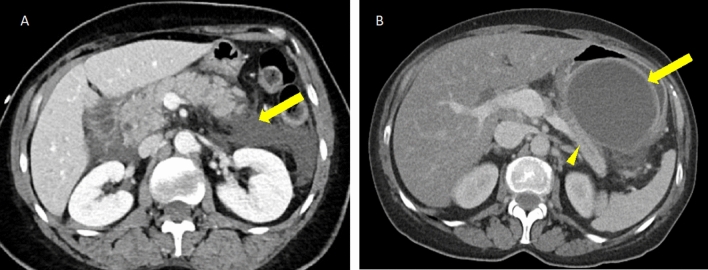

Fig. 9.

Acute interstitial edematous pancreatitis and necrotizing pancreatitis in two patients. A Axial IV contrast-enhanced CT in a patient with acute IEP showing peripancreatic stranding and fluid (arrow) and mildly heterogeneous enhancement of the pancreas (arrowhead). B Axial IV contrast-enhanced CT in a patient with acute NP showing a large area of non-enhancement of the pancreas and peripancreatic stranding (arrow). A small area of enhancing pancreatic parenchyma is seen in the pancreatic head (arrowhead)

Fig. 10.

Peripancreatic collections in interstitial edematous pancreatitis. A Axial IV contrast-enhanced CT in a patient with acute IEP and simple, homogeneous fluid density peripancreatic collections (arrow). B Axial IV contrast-enhanced CT in a patient with a history of IEP beginning 8 weeks ago showing a homogeneous fluid density peripancreatic collection (arrow) abutting the pancreatic body (arrowhead) with an enhancing capsule/rim, compatible with a pseudocyst